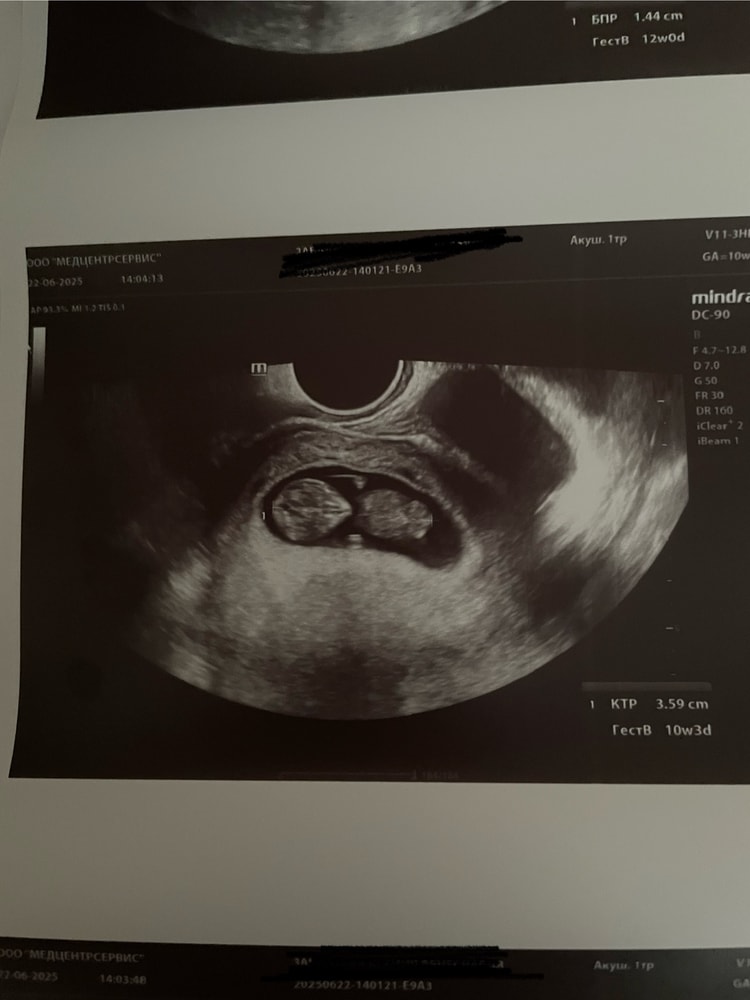

Вопросы могут быть по прикреплению плаценты, наверное. Близко к зеву ШМ